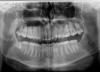

ПациентД Опубликовано 19 марта, 2013 Поделиться Опубликовано 19 марта, 2013 (изменено) Сказали удалить изначально 8ку сверху справа (якобы он будет травмировать нижнюю 8ку), а потом уже удалить нижнюю восьмерку.Так ли это и что Вы, уважаемые форумчане, посоветовали бы? Изменено 19 марта, 2013 пользователем ПациентД Ссылка на комментарий

Afffinity Опубликовано 19 марта, 2013 Поделиться Опубликовано 19 марта, 2013 Советую удалить все восьмерки. Нижнюю в 1 очередь. 2 Ссылка на комментарий

IvanK Опубликовано 19 марта, 2013 Поделиться Опубликовано 19 марта, 2013 Советую удалить все восьмерки. Нижнюю в 1 очередь.+1удалять нужно все 8-ки 2 Ссылка на комментарий

Mane Опубликовано 21 марта, 2013 Поделиться Опубликовано 21 марта, 2013 Все три восьмерки удалять 1 Ссылка на комментарий